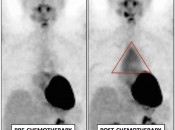

- Assess Response to Therapy

3. Timing of PET/CT Exam After Therapy

- “Rule of 3”

- Chemotherapy: 1 month

- Surgery: 2 months

- Radiation: 3 months